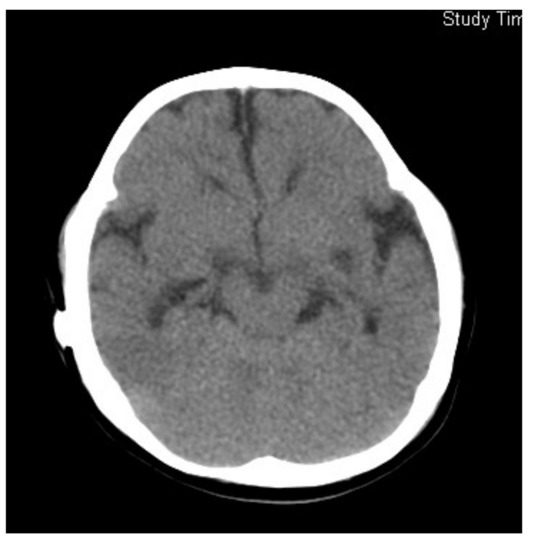

Figure 2.

Brain MRI of Case 2. (a) At 2.5 months of age (T1); (b) 4 months of age (T1) showing no effect on the ventricular size after ventricular drainage.

The administration of betaine monohydrate (100 mg/kg/day) was started at 4 months of age, and her respiratory status and vitality improved rapidly. Sanger sequencing of the methylenetetrahydrofolate reductase gene (MTHFR) detected a homozygous variant, c.466_467GC > TT, and both parents were found to be heterozygous carriers of this variant. Based on the diagnosis of homocystinuria type III caused by MTHFR deficiency, betaine therapy was continued at the dosage of 300 mg/kg/day, which raised plasma Met levels to 14–40 μmol/L, and reduced plasma tHcy concentrations to 50–110 μmol/L. Head MRI at the age of 12 months revealed the almost complete resolution of ventricular enlargement and atrophic changes (Figure 3). However, severe psychomotor retardation became evident, with a development quotient of 36 at the age of 1 year and 4 months. Epileptic seizures also appeared at the age of 3 years, so the administration of sodium valproate was added. This case was reported previously [9].